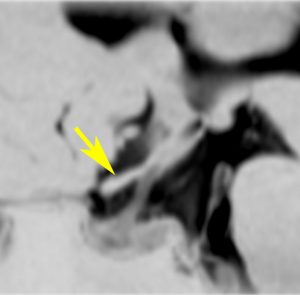

眼窩内単視神経膠腫

1歳児の左眼窩内単視神経膠腫です。左目は手動弁程度ですから,全摘出しました。まぶたの動きと眼球運動は温存しました。この例に何年も化学療法を続けるのは馬鹿げています。

左の写真は,左眼窩内腫瘍,右の写真は,頭蓋内の正常左視神経です。